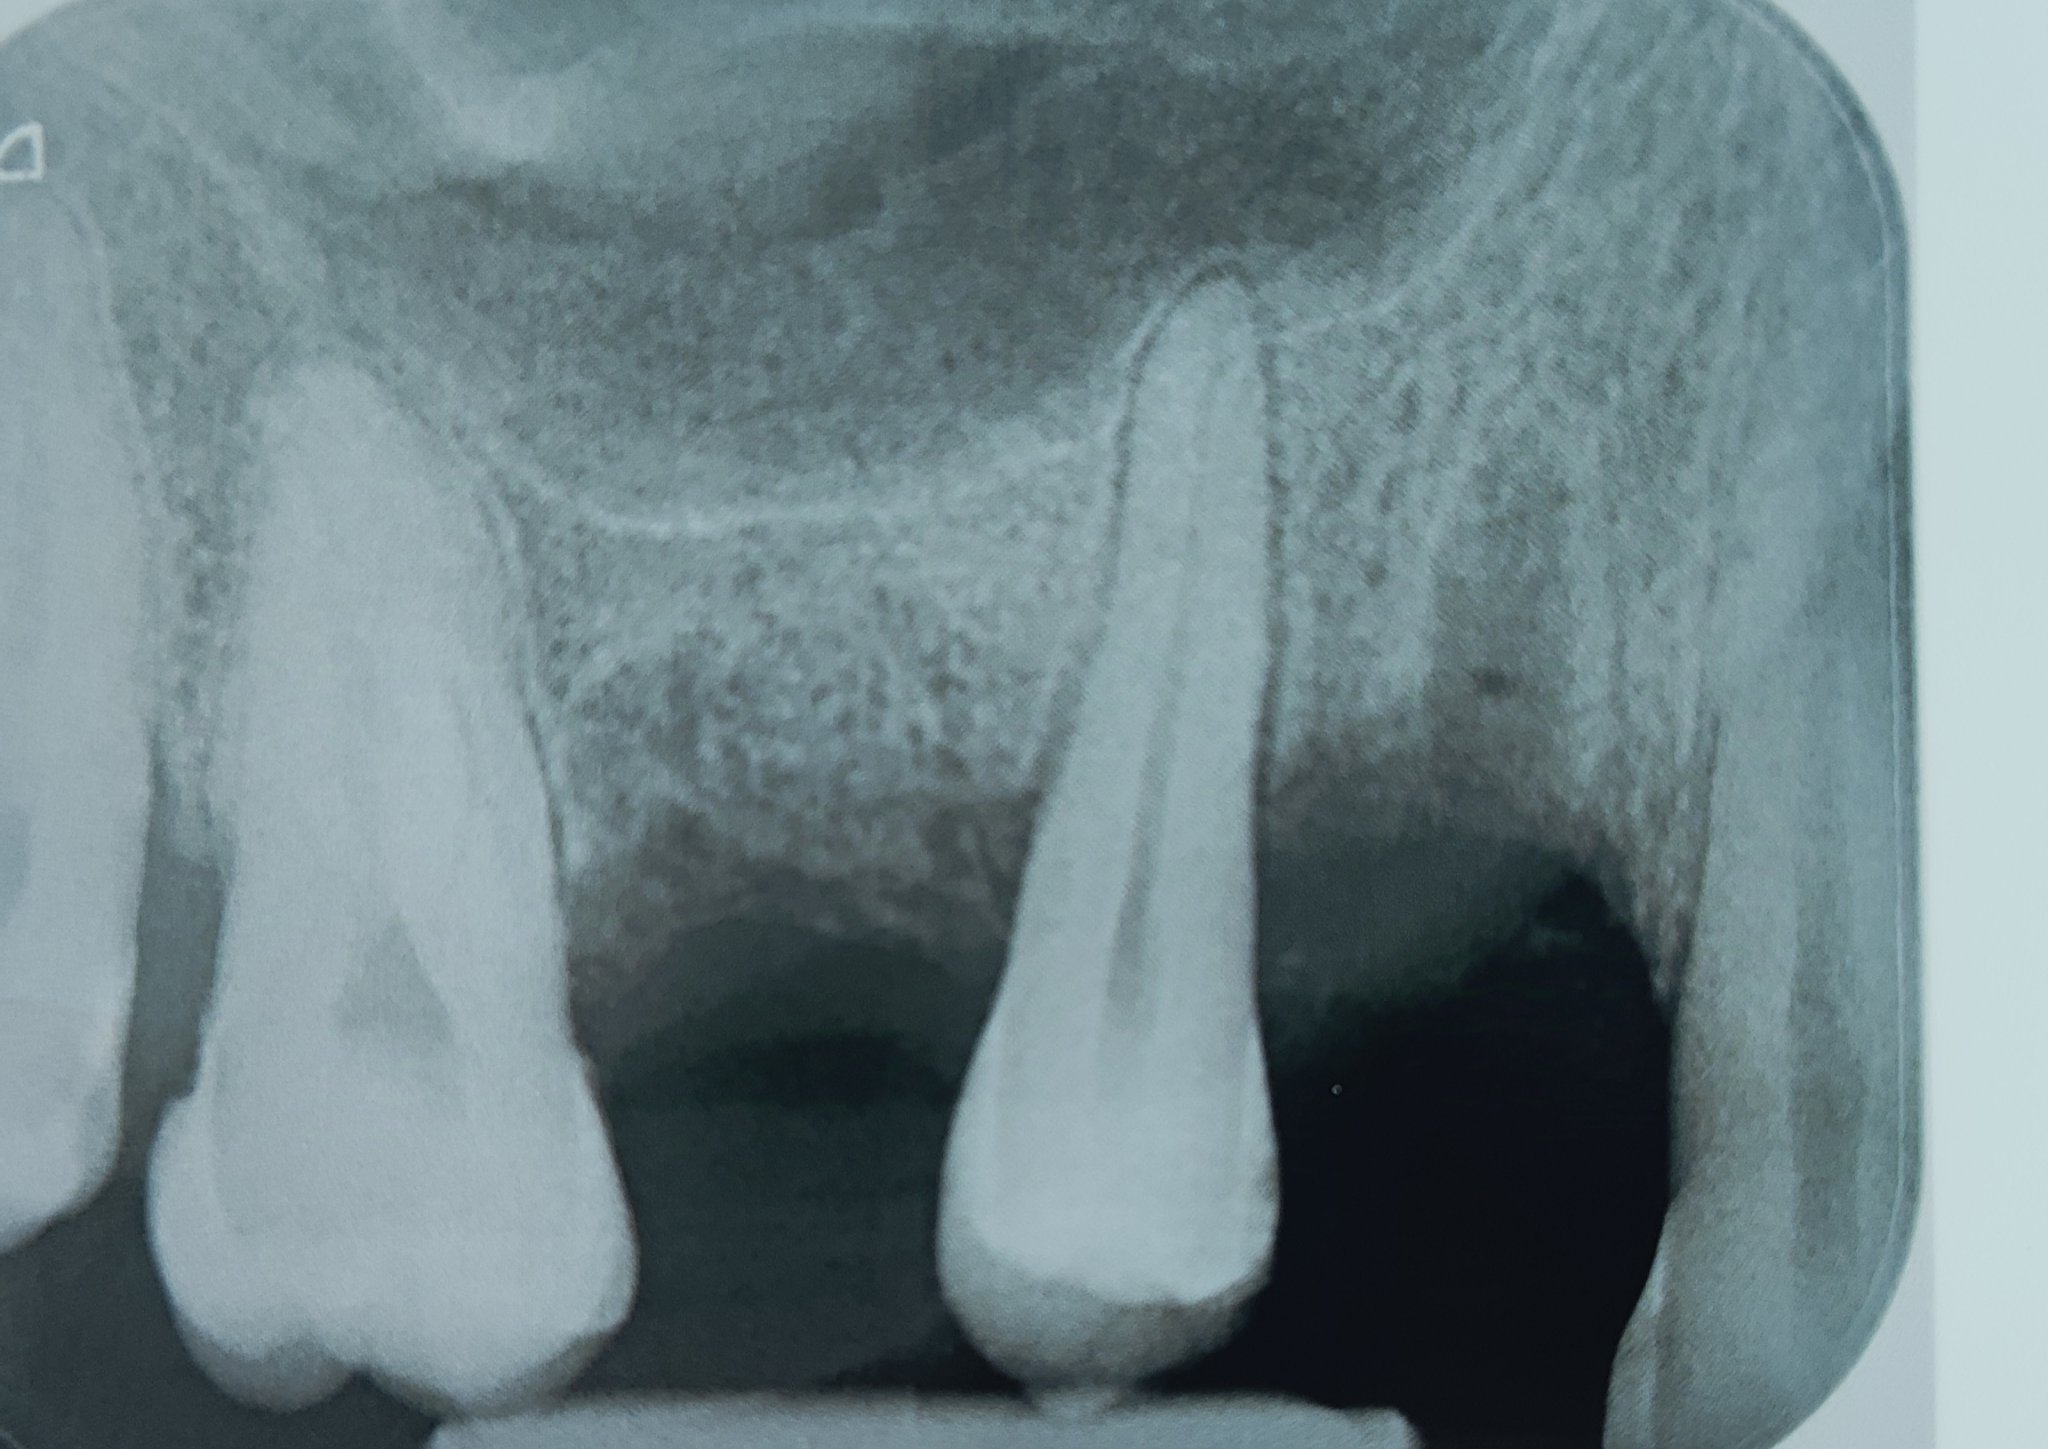

Болка при натиск и дъвчене. Отпусна ме леко от аулин снощи. Не е остра като на нерв... все още

Ивайло, ще ходя, но искам да знам дали може да изчака до другата седмица. С часовете не е много лесно. Аз не виждам гранулом на снимката, но е факт, че ме боли при натиск. Поне не пулсира.